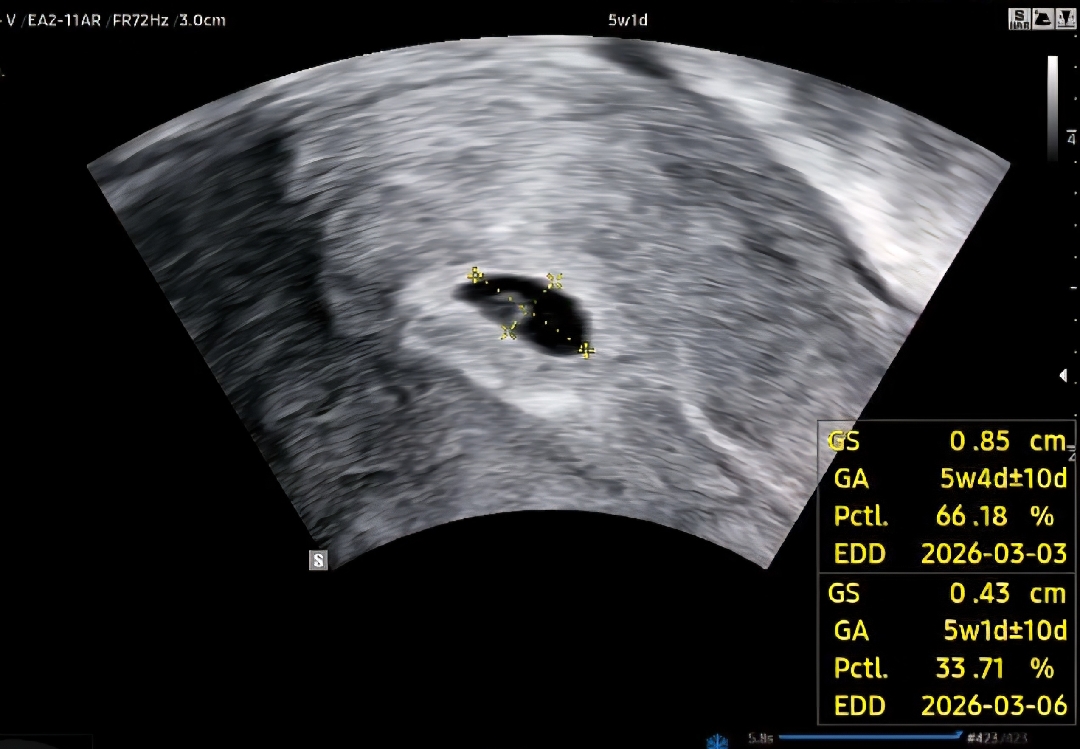

5주 1일차 초음파봤어요

막생 5.30일 7.5일 토요일에 아기집이랑 초음파 봤어요 다음주에는 심장소리 들을 수 있겠죠? ㅠㅠ 심소까지 듣고 회사에 알리면 너무 늦을까요..